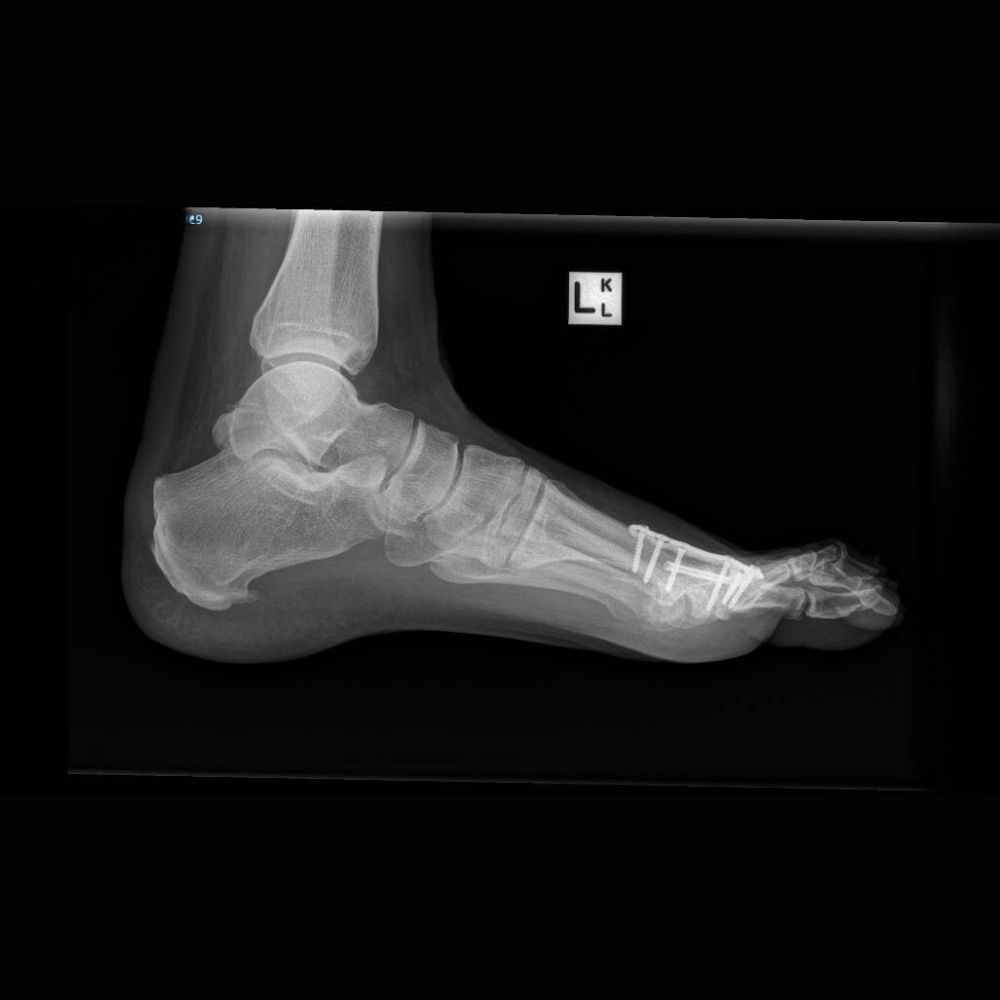

Flat Foot in a 16 year old girl with Cerebral Palsy